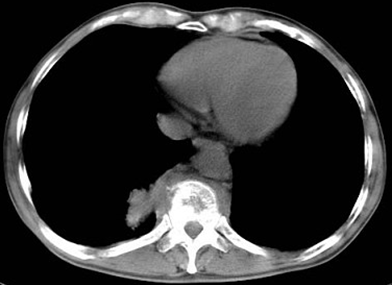

男,32岁,低热、乏力,背痛,活动受限,结合CT检查选择最可能的诊断()

A.化脓性脊柱炎

B.脊柱转移瘤

C.椎体压缩骨折

D.椎体结核

E.类风湿关节炎